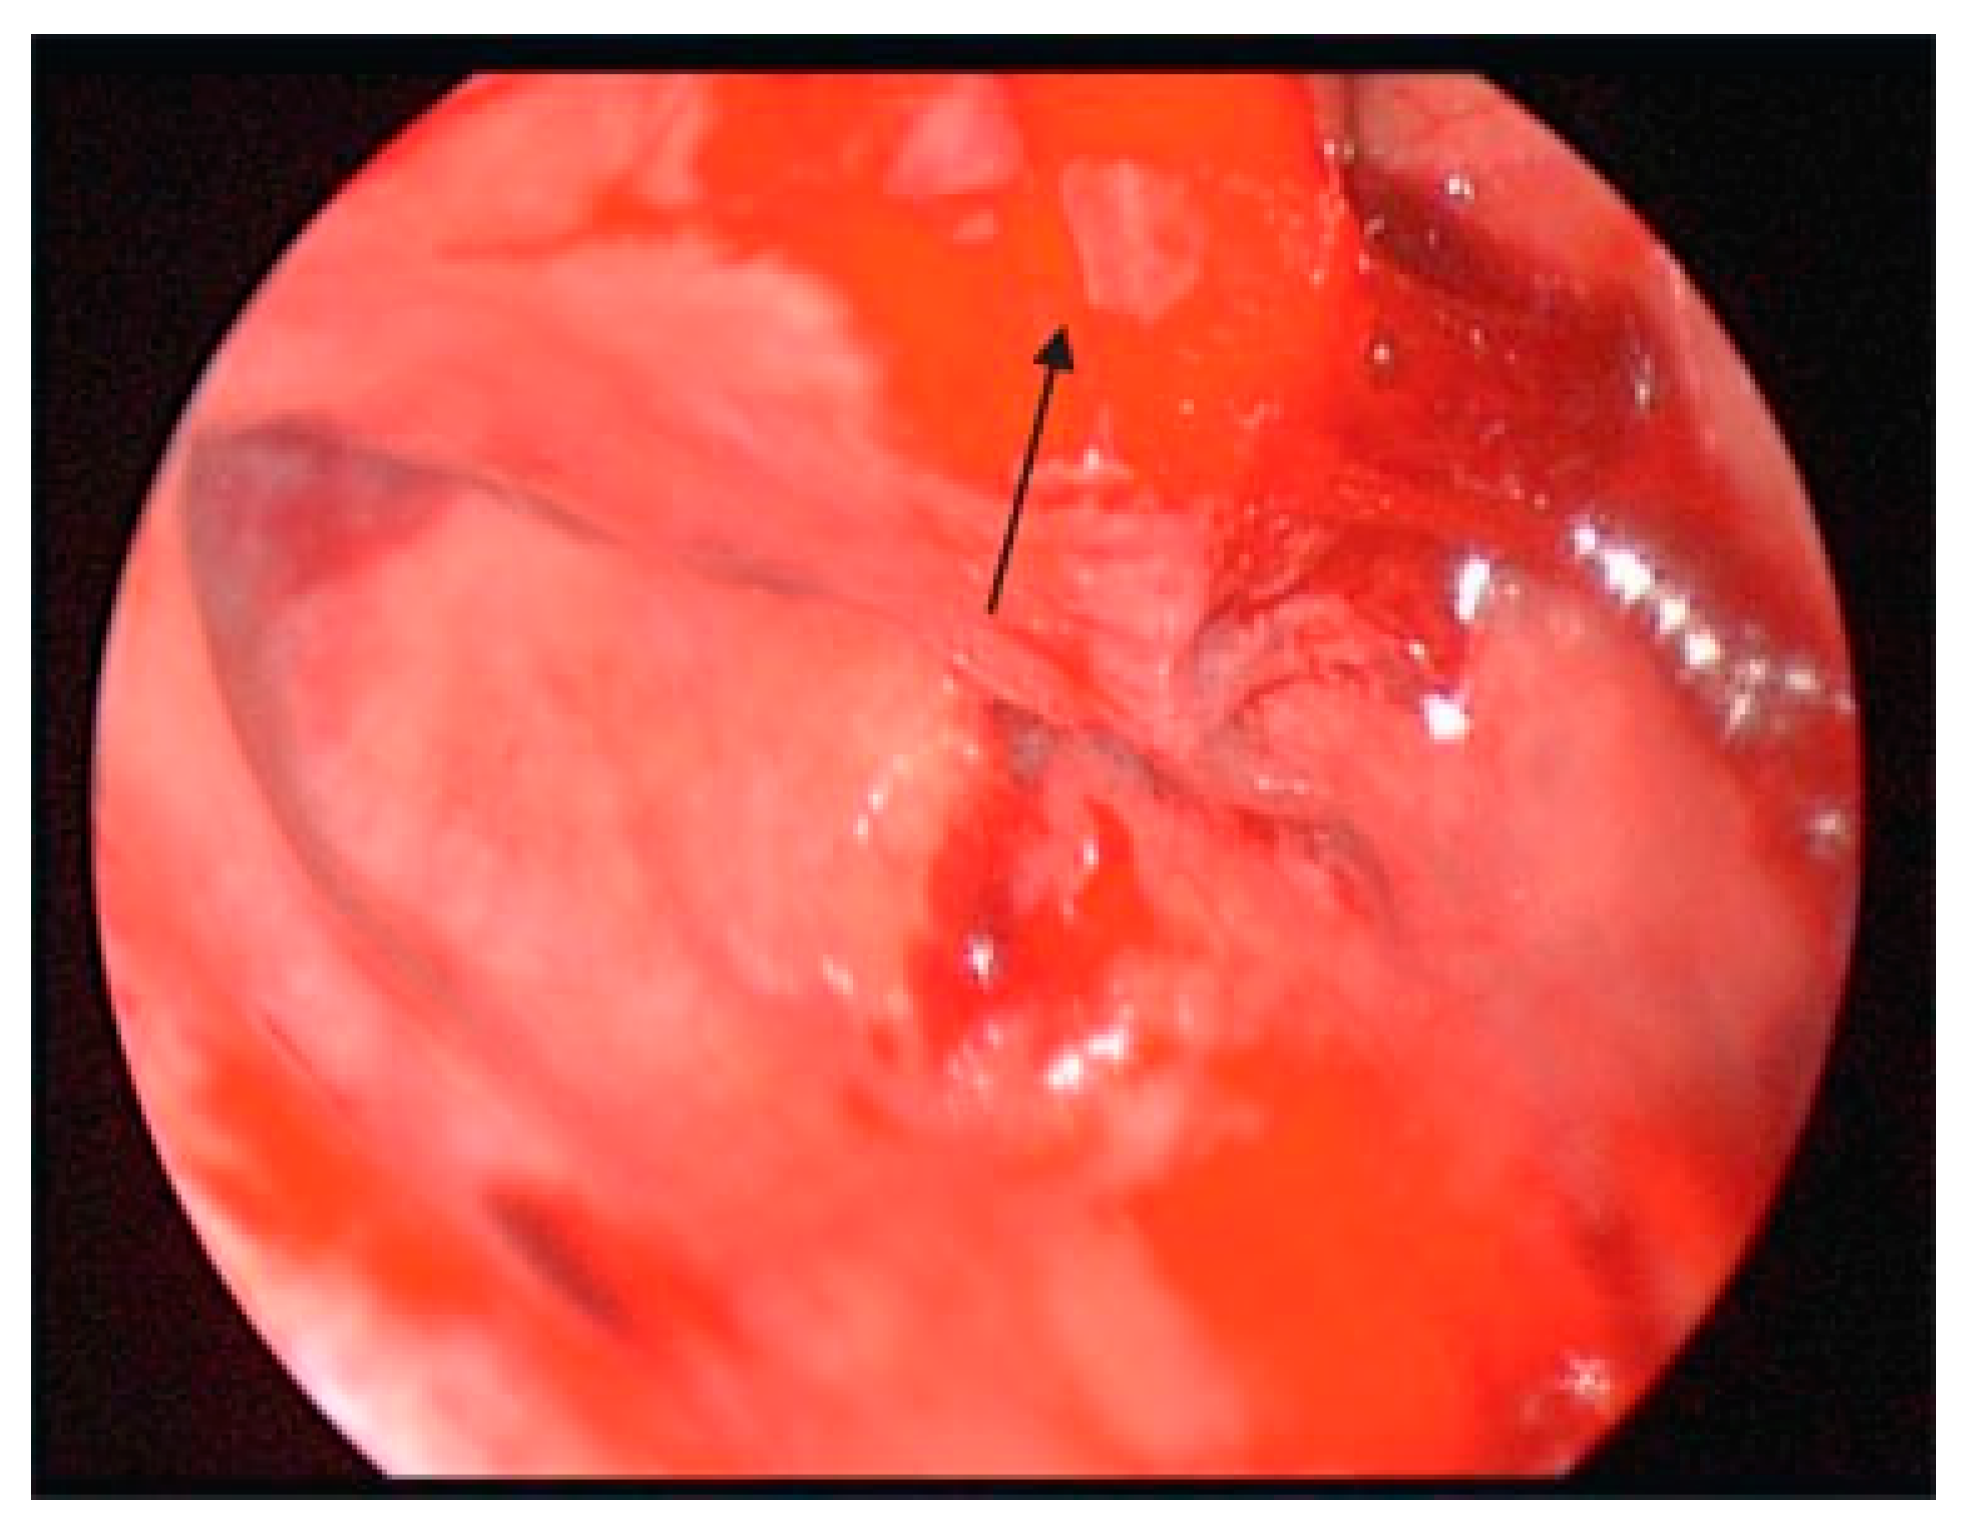

Medial orbital fractures are treated similarly to floor fractures except that these require more extensive knowledge of intranasal anatomy. To undertake the endoscopic repair, you must be aware of endoscopic skull base anatomy and be comfortable taking or medializing the middle turbinate and taking the uncinate process and ethmoid bulla down (Figure 8). If you can do this, you can have a full view of the lamina papyracea (Figure 9). Once the lamina is identified, you can ballot and find the defect. This is then most easily repaired with a Silastic sheet of sufficient stiffness to prevent herniation of the orbital contents. A thin Medpor sheet may also be used (Figure 10).

Figure 10. Medpor plate in place.